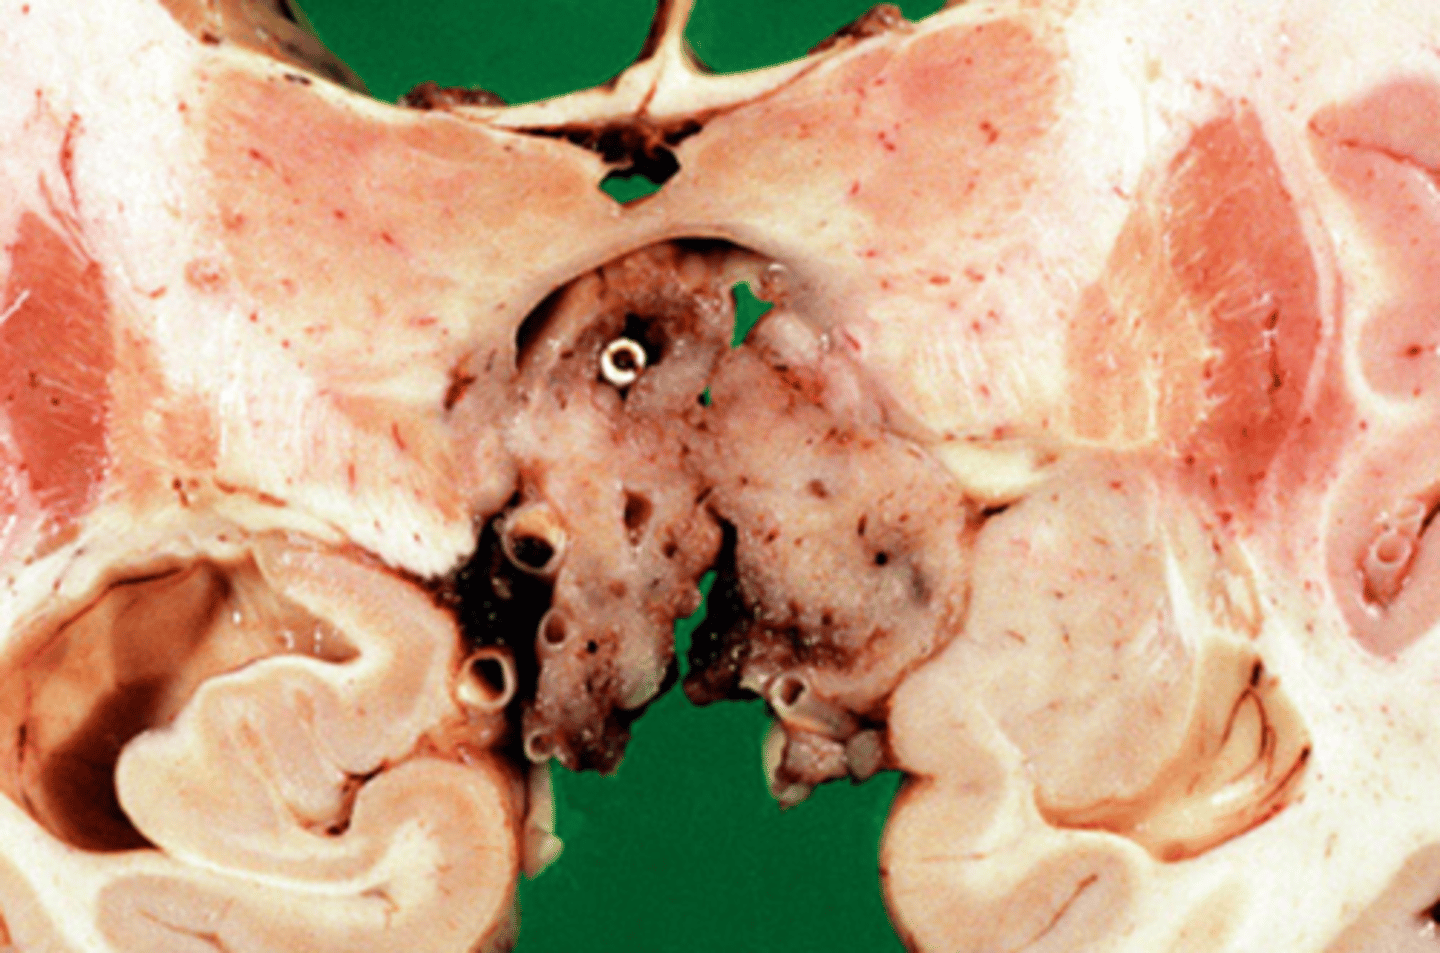

Adrenal neuroblastoma

Pathology?